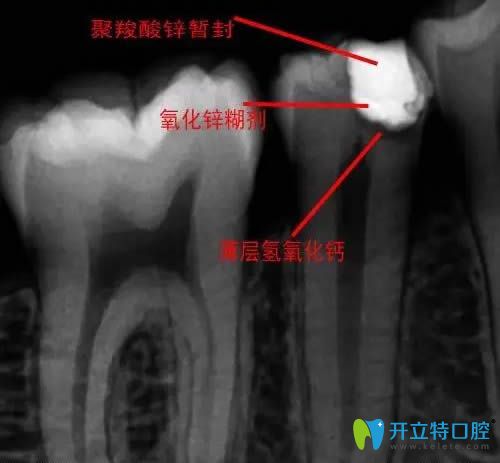

牙齒蓋髓術(shù)圖解

一種保存牙齒活髓的方法,是把蓋髓劑覆蓋在即將暴露或已穿露的牙髓部位,使其創(chuàng)面上的病變消除。常用的蓋髓劑有氫氧化鈣制劑或氧化鋅丁香油糊劑等,均有較強(qiáng)的殺菌、抑菌能力和滲透作用,可促進(jìn)牙髓組織再生,目的就是為了保存活的牙髓組織保留患牙。通俗來講,就像是把草藥敷在傷口上,這樣既能療傷又能避免傷口感染。

直接蓋髓術(shù)拍片圖解